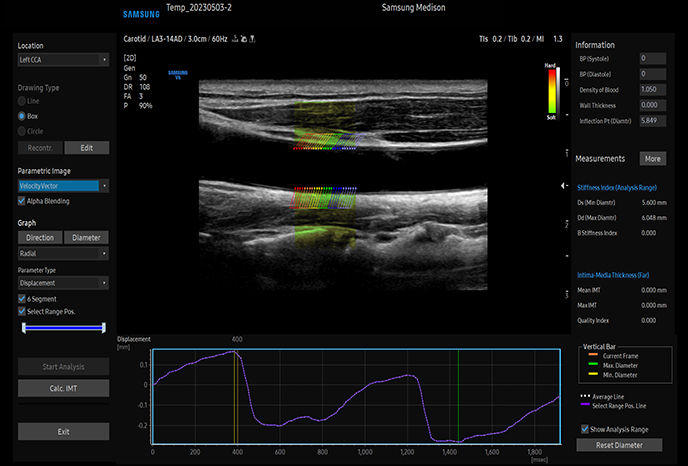

하이앤드 초음파 장비를

활용한 정밀 심장 검사

심장 질환 진단에서 가장 중요한 것은 ‘심장의 상태를 얼마나 정확하게 볼 수 있느냐’입니다. 저희 센터는 대학병원급 하이앤드 초음파 장비를 도입하여, 실시간 3D 렌더링으로 정밀 진단이 가능하며, 심장의 구조·혈류·기능을 실시간 고해상도로 관찰합니다.

미세한 판막 움직임, 혈류 속도 변화, 심방·심실 크기와 수축력까지 정밀하게 분석할 수 있어, 심장질환의 조기 발견과 치료 계획 수립에 큰 차이를 만듭니다.